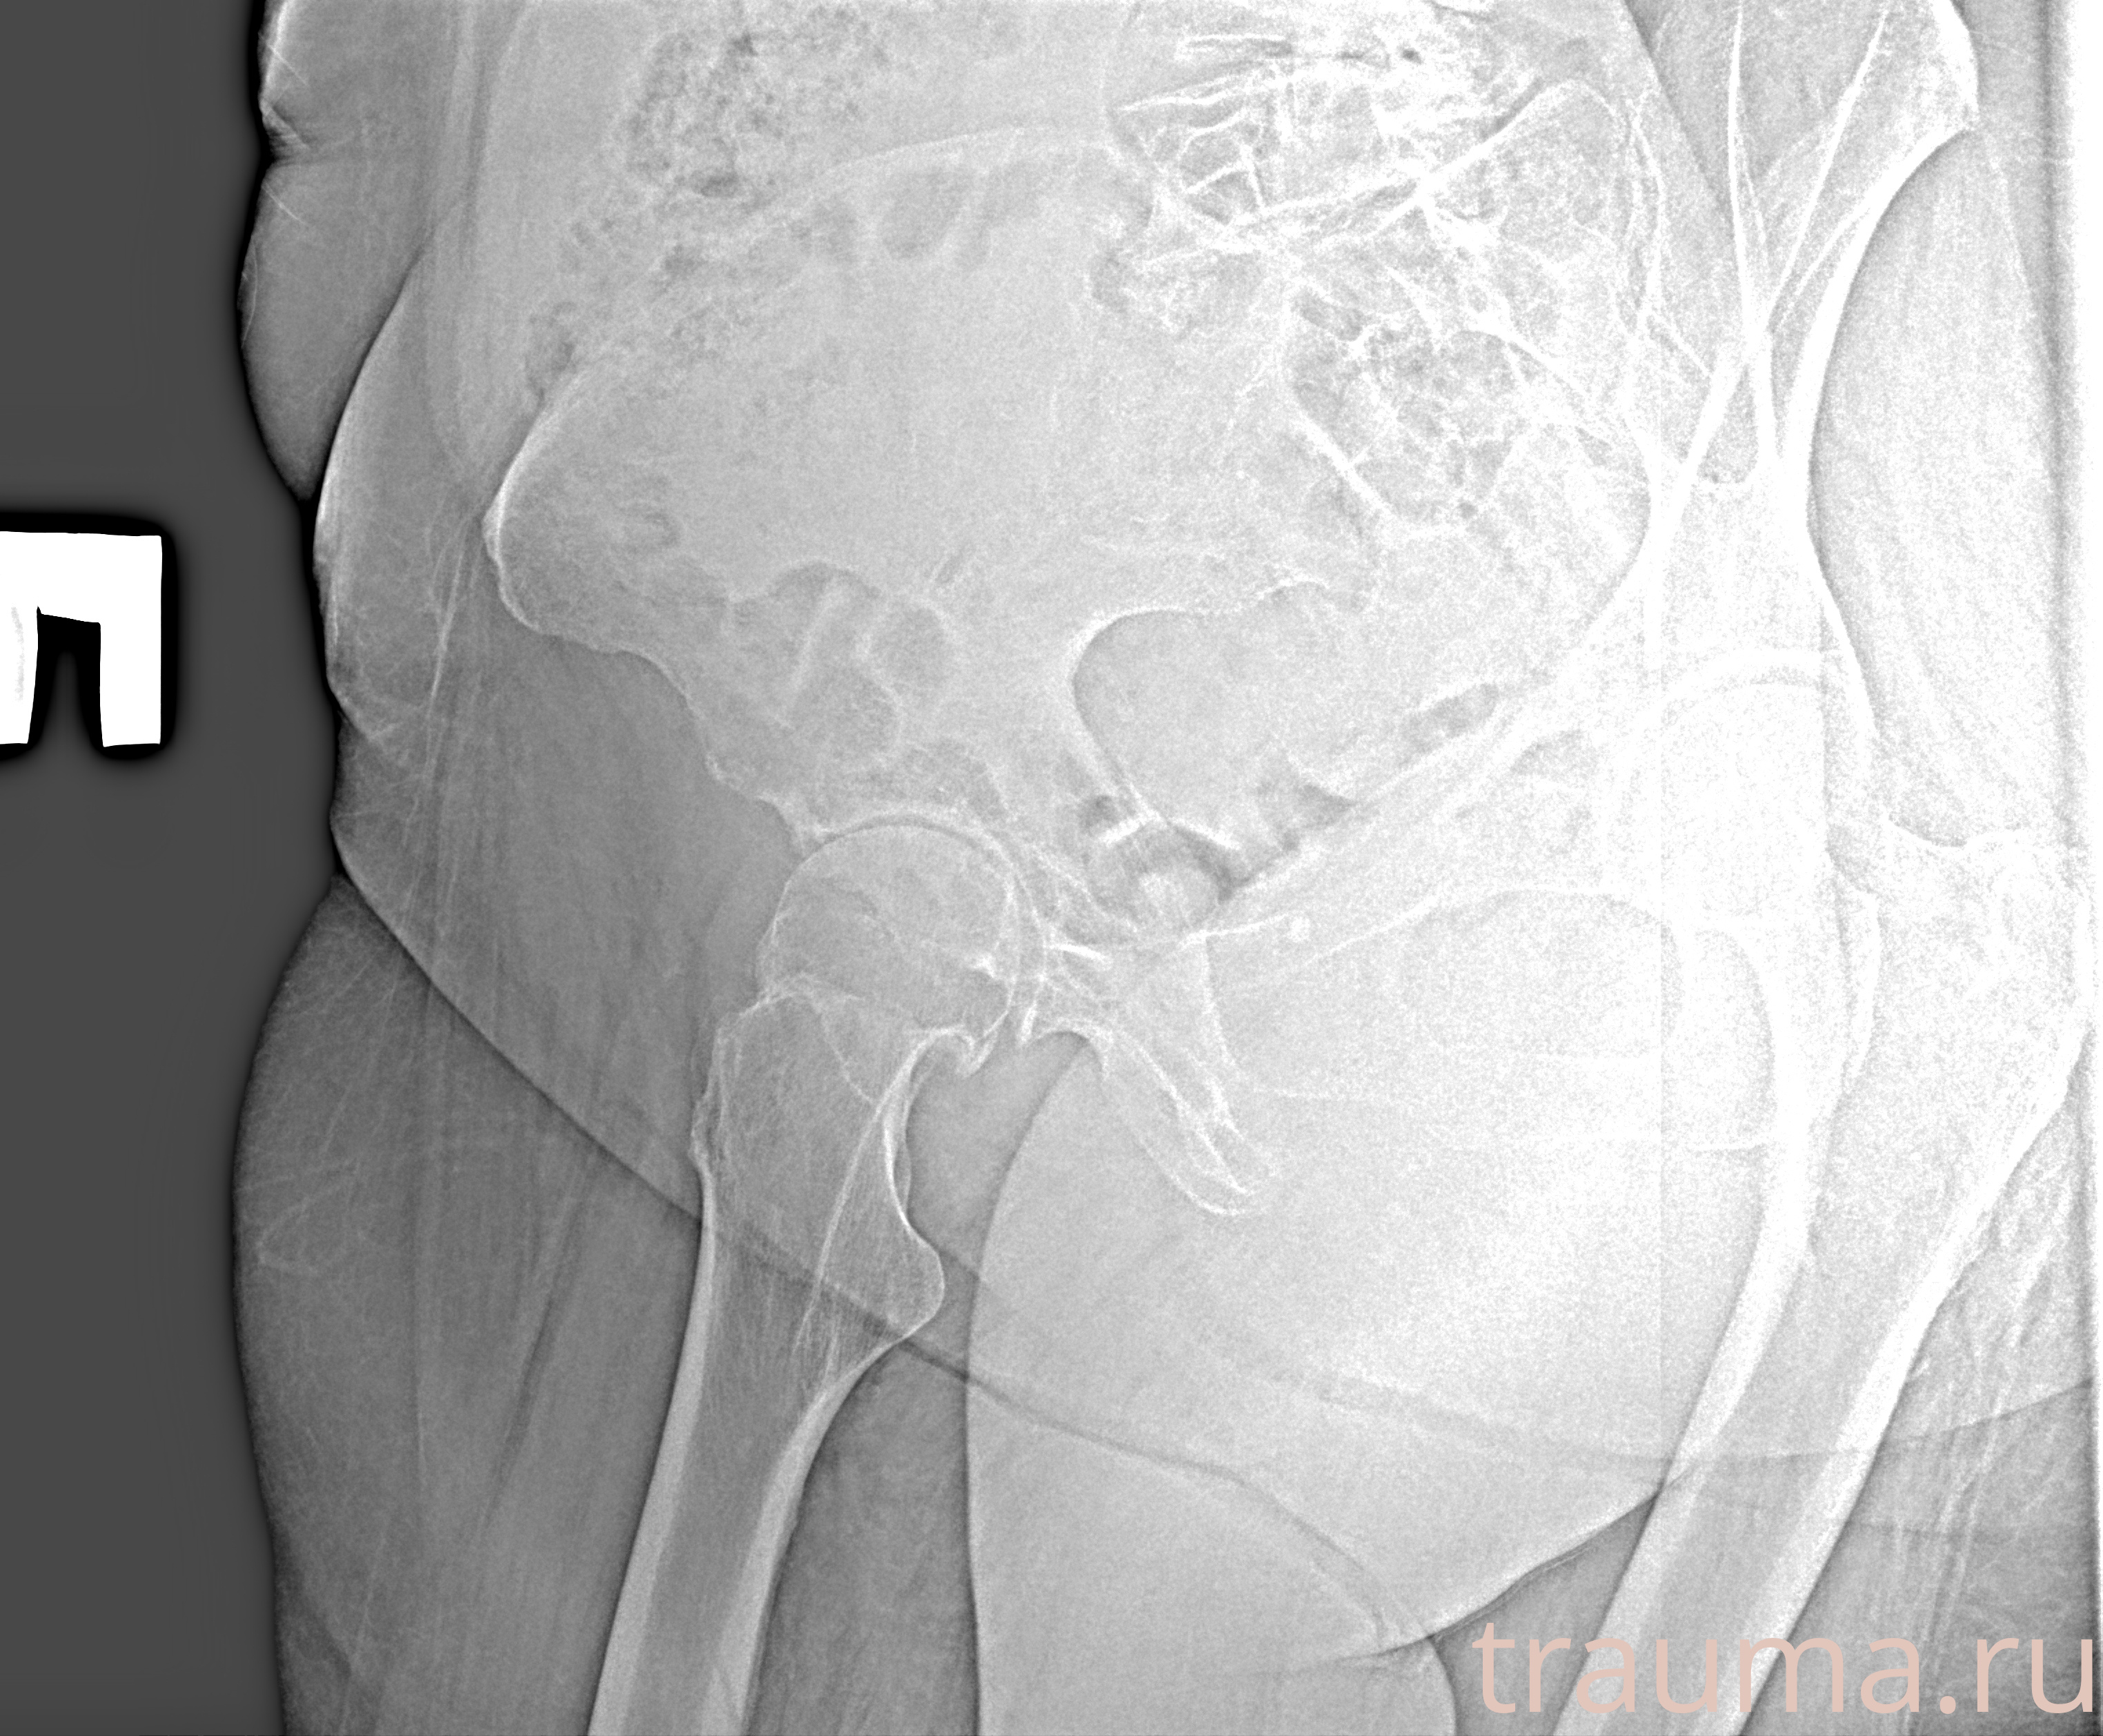

Первая помощь при переломе шейки бедра

Рентген на дому: по вашему адресу приезжает врач-рентгенолог, травматолог-ортопед с мобильным рентгеновским аппаратом, проводит диагностику травмы или заболевания, делает необходимые рентгенограммы, дает рекомендации по дальнейшему лечению. Получить качественные снимки в домашних условиях возможно благодаря уникальной методике, разработанной МосРентген Центром для института  Склифосовского